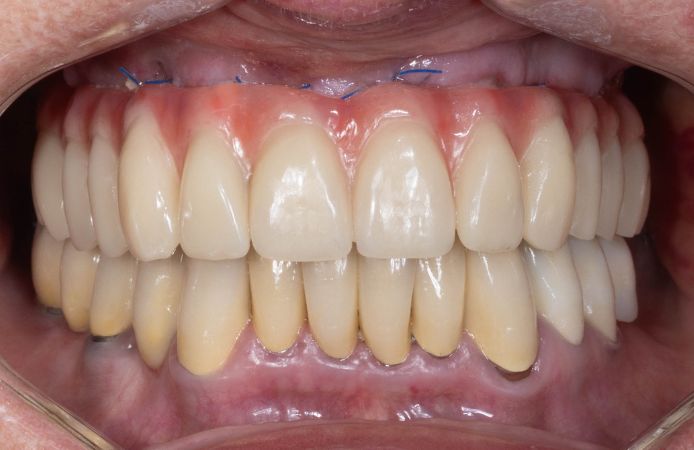

The provisional restoration was delivered the day after surgery. Facial view.

Figure 18.

Facial view of patient when removing stitches 7 days after surgery.

Downloads